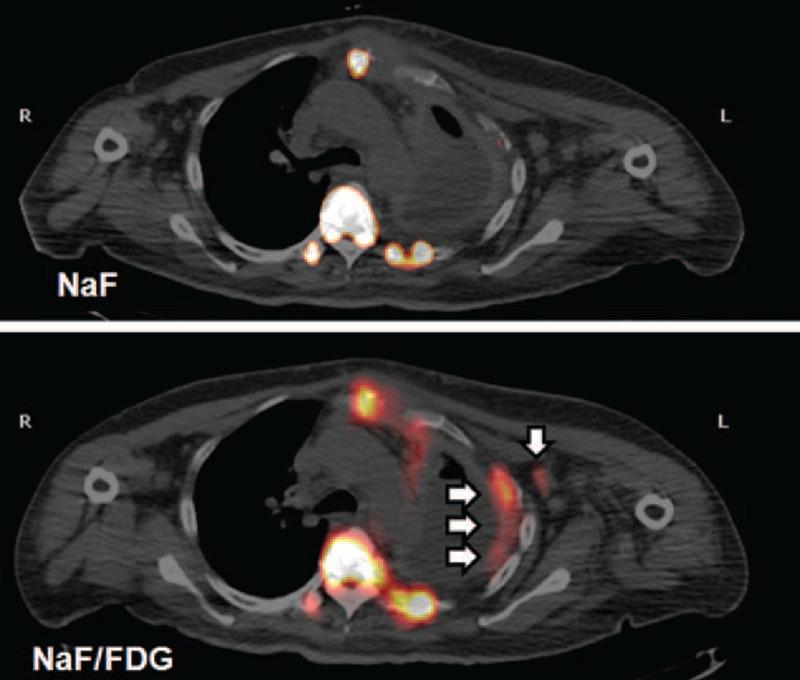

Current nuclear imaging of the skeletal system is achieved using technetium-99m (Tc-99m) methylene diphosphonate (MDP), F-18 sodium fluoride (NaF), or F-18 fluorodeoxyglucose (FDG). However, comparisons of these are rare in the literature. We present a case of a 51-year-old female with suspicious lung cancer due to main symptoms of dyspnea, nonproductive cough, and pleural pain. Tc-99m MDP whole-body bone scan (WBBS) showed multiple bony metastases. Five days later, positron emission tomography/computed tomography (PET/CT) images using both F-18 NaF and a cocktail of F-18 NaF and F-18 FDG were obtained on the same day 2 hours apart. The former showed more foci and precisely showed bony lesions compared to those obtained using Tc-99m MDP WBBS. However, the latter demonstrated more extensive radiotracer uptake, especially in osteolytic lesions, and additional soft tissue lesions in the left axillary and surpraclavicular nodes as well as the left pleura. Surgical biopsy was performed in left axillary nodes, and the metastatic carcinoma was found to be of breast origin. This case demonstrated that a cocktail of F-18 NaF and F-18 FDG could be useful in PET/CT for not only detecting more skeletal lesions but also guiding biopsies accurately to the affected tissue.

目前,骨骼系统的核成像采用锝-99m(Tc-99m)亚甲基二膦酸盐(MDP)、F-18氟化钠(NaF)或F-18氟脱氧葡萄糖(FDG)来实现。然而,文献中对这些方法的比较很少。我们报告一例51岁女性,因呼吸困难、干咳和胸痛等主要症状怀疑患有肺癌。Tc-99m MDP全身骨扫描(WBBS)显示多处骨转移。五天后,同一天相隔2小时分别获得了使用F-18 NaF以及F-18 NaF与F-18 FDG混合剂的正电子发射断层扫描/计算机断层扫描(PET/CT)图像。与使用Tc-99m MDP WBBS获得的图像相比,前者显示出更多病灶,并能精确显示骨病变。然而,后者显示出更广泛的放射性示踪剂摄取,尤其是在溶骨性病变中,以及左腋窝和锁骨上淋巴结以及左胸膜处的额外软组织病变。对左腋窝淋巴结进行了手术活检,发现转移癌起源于乳腺。该病例表明,F-18 NaF与F-18 FDG的混合剂在PET/CT中不仅有助于检测更多的骨骼病变,还能准确地引导对受影响组织进行活检。